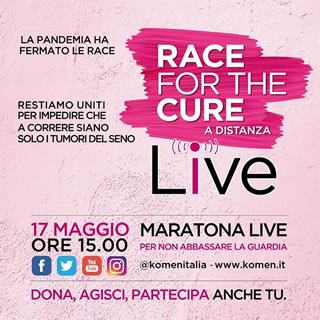

Domenica 17 maggio seguiamo la maratona su tutti i social @komenitalia e su www.komen.it/race-live a partire dalla mattina con l'anteprima "aspettando la Race" e dalle 15.00 per la RACE LIVE